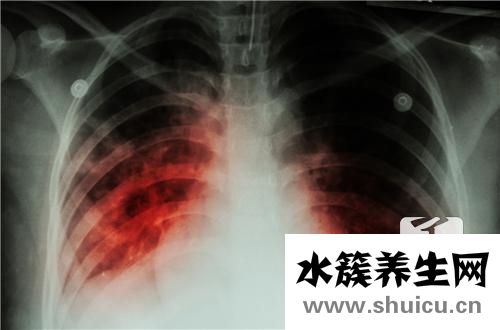

肺結核這類病癥具備極強的感染性,它能夠 根據空氣傳播,會對身邊的人導致十分大的影響,因此 當得了這類病癥以后,一定要嚴加防范,盡量減少病癥的散播。而且在平時的日常生活,要多學習培訓關于肺結核的專業知識,掌握肺結核散播的方式,這針對疾病的治療有十分大的協助。

那麼患肺結核能夠 過夫妻生活嗎?肺結核病人在活躍期,感染性十分的強,能夠 根據呼吸系統及其口水散播,因此 在這個時間范圍以內,千萬別開展夫妻生活,不然那般非常容易造成病況的交叉式感染,進而給醫治導致十分大的困惑。可是假如病人醫治了六個月以上,而且歷經查驗后人體內沒有結核菌的排出來,那麼就可以適當的開展夫妻生活,這個時候病況早已基本獲得控制,不容易再導致病癥的散播??墒歉扇f不能夠性生活頻繁,不然那般會造成人體抵抗能力越差,進而導致病發癥的產生。

肺結核的防止也十分關鍵。針對肺結核這類病癥而言,最好是的防止方式便是注射卡介苗,那樣能夠 讓人體得到結核菌的抗原體,進而防止結核菌的感染,那樣能夠 大幅度降低患肺結核的概率。此外,也要留意生活起居中的醫護,平常應當搞好防凍保暖的對策,盡量減少發燒感冒受涼,不然那般非常容易造成呼吸系統產生感染,進而導致肺結核的產生。而且還應當積極主動的報名參加鍛煉身體,多開展戶外活動游戲,以提高體質,增強免疫力,這針對預防肺結核的產生也是有十分大的協助。

總得來說,假如病人的肺結核在活躍期,那麼千萬別開展夫妻生活,由于這非常容易造成病癥的散播,乃至還會繼續導致交叉式感染,進而給病況的醫治帶來不利的影響。在平時的日常生活當中,最好是根據注射卡介苗來預防肺結核這類病癥,那樣能夠 大大減少肺結核的感染概率,針對維護的身心健康有十分大的協助。